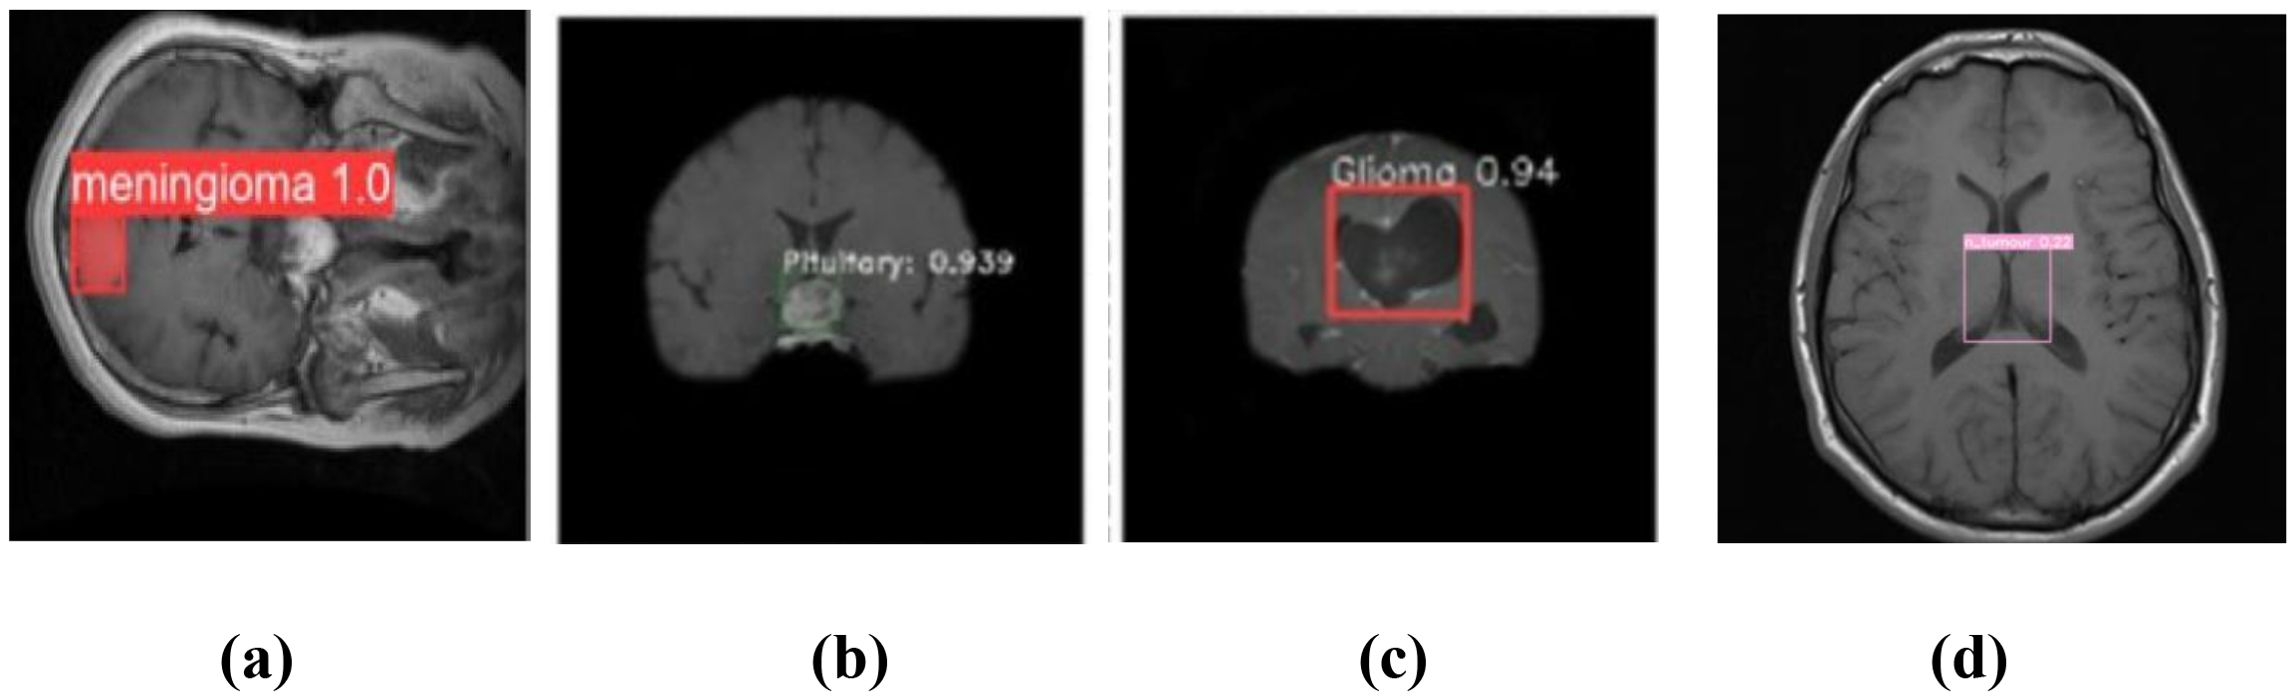

The YOLOv7 model’s forecast is shown in Figure 5. These were used to maximize computational effectiveness and speed up inference, making it possible to identify instances in a variety of images. The anticipated images demonstrated the accuracy with which the brain tumor identification system operated following its training on the initial images. The complete outcomes of classification using the YOLOv7 model are presented in Figure 6. The experiment’s findings proved that YOLOv7 produced useful outcomes.

Figure 5. Prediction of brain tumor using YOLOv7 model: (a) meningioma, (b) pituitary tumor, (c) glioma, and (d) no tumor.

Observation: Accurate bounding boxes drawn over tumors with correct class labels.

Decision: Demonstrates the model’s potential for assisting in real-time clinical diagnosis.